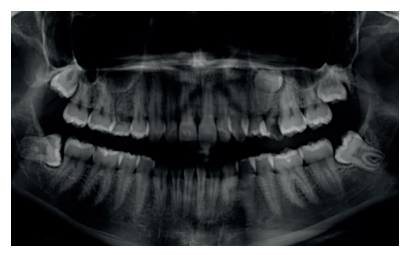

Se presenta un caso clínico de una mujer de 20 años de edad, que acudió remitida por su ortodoncista para la extracción de un premolar retenido maxilar, en posición invertida, previo a la realización de tratamiento ortodóntico. Se realizó la Historia Clínica de la paciente, que no presentó antecedentes médico-quirúrgicos de interés, alergias medicamentosas conocidas ni hábitos nocivos. A la exploración extraoral no se apreció ningún dato relevante. A la exploración intraoral, la paciente presentó la ausencia en boca del segundo premolar superior izquierdo y la presencia de los terceros molares inferiores retenidos (Figuras 1, 2 y 3).

A la exploración radiográfica mediante radiografía panorámica se apreciaron ambos terceros molares inferiores retenidos, en una posición mesioangular, los superiores retenidos en posición vertical y la presencia de un premolar maxilar retenido, en posición invertida, en el segundo cuadrante (Figura 4).